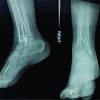

His vitals were stable. Tense diffuse swelling around ankle was present. Tenderness was present over the lateral malleolus and over the heel. Attempted ankle movements were painful. There are no distal neurovascular deficits. The ankle was immobilized in below-knee plaster splint and radiographs were taken after stabilizing the patient. X-ray showed lateral talar process fracture with probable fracture line extending into body (Fig.2).